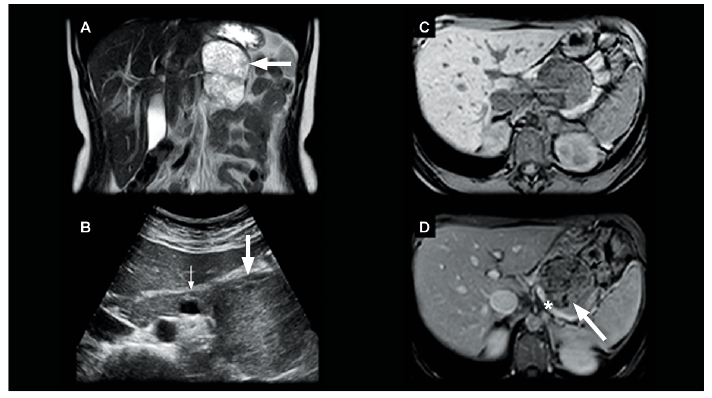

Paciente de sexo femenino de 41 años, sin antecedentes mórbidos de relevancia, que consulta de forma ambulatoria por epigastralgia intermitente de un mes de evolución. Al examen físico y de laboratorio no hay hallazgos significativos. Se solicitó una ecotomografía de abdomen, que informó la presencia de una masa heterogénea en el cuerpo-cola del páncreas (Figura 1).

Se realizó una resonancia magnética (RM) de abdomen, que confirmó la presencia de una masa sólido-quística hipovascular, encapsulada, dependiente del aspecto anterior del cuerpo-cola del páncreas (Figuras 1 y 2), cuyos componentes sólidos restringían en la secuencia de difusión (DWI/ADC), presentando algunos tenues focos de alta señal en secuencias ponderadas en T1 que hacían suponer la presencia de residuos de material hemático en su espesor. Esta masa medía 7,9 x 5,4 x 6,6 cm en sus ejes mayores e indentaba ampliamente la vena esplénica, sin obliterarla ni infiltrarla (Figura 1). El resto del parénquima del páncreas mantenía una arquitectura y señal normales, sin dilatación del conducto pancreático principal, adenopatías retroperitoneales ni ascitis.